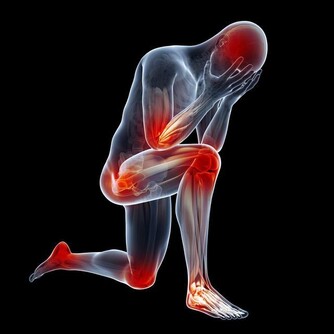

經常久坐,尤其是對我們的腿部健康不利。不管是年輕人還是老年人,你會發現,久坐之後,尤其是我們的下肢感受會比較深,坐久了並不舒服,反而還出現了腿麻、腿腫痛的情況。

這是因為什麼呢?其實道理非常簡單,當我們一直久坐的時候,我們身上有很多的血管,而血液流通也是時時刻刻的。我們一直保持一個姿勢,人在坐著的狀態下,血液流向的地方比較多的就是雙腿了。

沒有了運動的支持,下肢的血液循環變慢,就容易讓血管變得擁堵。在臨床上也發現,靜脈曲張、下肢血栓的人,最好不要久坐、久站,更不要久躺,久躺在這3個方式當中,算是可以讓機體消耗熱量非常低的了,只會讓人越變越懶。

如果是比較嚴重的情況,還容易讓血管的血液流通變慢,增加血栓的發生危險。

對於年紀輕輕的人,也會因為不良的坐姿,增加頸椎、腰椎的壓力,容易罹患頸椎病、腰椎病,這也是我們大家不能忽視的。